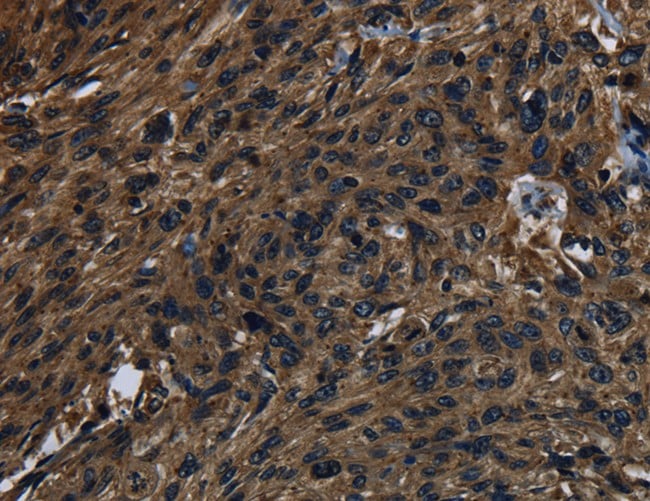

(Immunohistochemistry of paraffin-embedded Human esophagus cancer using KLK14 Polyclonal Antibody at dilution of 1:40)